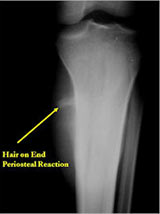

Plain X-Rays:

- Diaphyseal lesion on external surface of bone; medullary canal uninvolved

- Periosteal reaction usually most evident feature on surface of bone (Hair on End or Sunburst appearance with spiculated pattern of calcification oriented perpendicular to the bone)

- Spiculated or sunburst periosteal reaction (due to periosteal elevation)